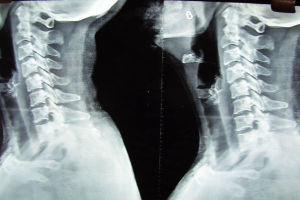

正常頸椎生理曲度從側方看人體在端坐或站立時的頸部似乎是直的,其實包繞於內的頸椎並不是直的,而是在其中段有一向前凸出的弧度。在醫學上把這一向前的弧形凸起稱為頸椎的生理曲度。通過X線片上的頸椎顯像:沿此曲度走行,在各個頸椎椎體後緣都有形成的連續 、光滑的弧形曲線,醫學上稱之為頸椎曲度。當長時間不正確的坐姿、或是長時間的勞累、頸椎缺少活動、脊柱損傷、脊柱鈣化等就會導致頸椎生理曲度變直。

頸椎生理曲度的存在,能增加頸椎的彈性,減輕和緩衝重力的震盪,防止對脊髓和大腦的損傷。由於長期坐姿、睡姿不良和椎間盤髓核脫水退變時,頸椎的前凸可逐漸消失,甚至可變直或呈反張彎曲,即向後凸,成為頸椎病X線上較為重要的診斷依據之一。

具有頭、肩、頸、臂的疼痛及相應的壓痛點,X線片上沒有椎間隙狹窄等明顯的退行性改變,但可以有頸椎生理曲線的改變,椎體間不穩定及輕度骨質增生等變化。此型在臨床上極為常見,是最早期的頸椎病。由於症狀較輕,往往重視不夠,以致反覆發作使病情加重,不少反覆落枕的病人即屬於此種改變。從大量的臨床觀察證實,此型實際上是頸椎病的最初階段,也是治療最為有利的時機。